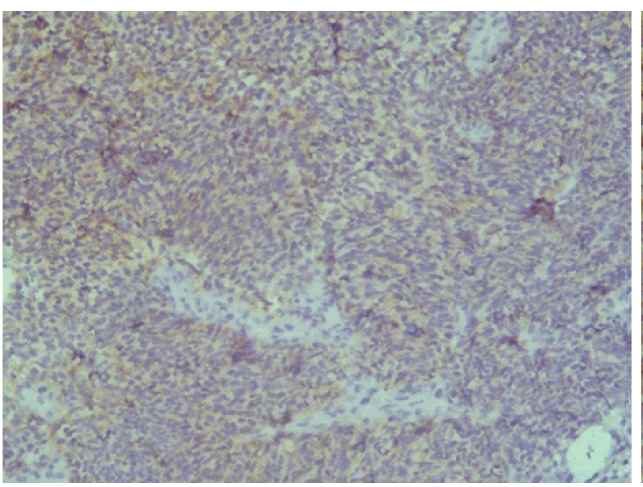

Поэтому при первичном гистологическом исследовании диагноз эстезионейробластомы был установлен только у 6 пациентов (66,6 %), у троих больных (33,4 %) были диагностированы другие формы злокачественного процесса, что не соответствовало клиническим проявлениям. Во всех случаях проводили иммуногистохимическое (ИГХ) исследование. ИГХ-исследование проводили на срезах с парафиновых блоков с использованием антител к Keratin.Pan (AE/AE3), CD45 (Cocktail), Synaptophysin (SP11), ChromograninA (SP12), CD56 (56C04), Ki-67 (30-9), p63 (7JUL)RTU, S100, INI1, CD99 (HO36-1.1). Также выполняли доставку с антителами к EMA (E29), TTF1 (8G7G3/1). В диагностических материалах была отмечена положительная экспрессия Synaptophysin, ChromograninA, CD56, Ki-67 (до 90% ядер), INI1 (рис. 2–6).

Рис. 2. Synaptophysin [SP 11] ×200

Рис. 3. Chromagranin A [SP 12] ×200

Эти результаты иммуногистохимического исследования подтверждают наибольшее соответствие иммунофенотипа опухоли – ольфакторной нейробластоме (G3 по Hyams) М9522/33.